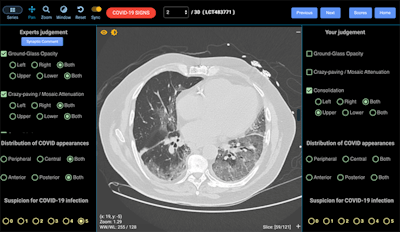

The training module comprises 30 clinical images drawn from the global image bank. Participants are asked to describe each image in turn by clicking on various description boxes, such as ground-glass opacities, crazy paving, and consolidation. They are also asked to define the distribution by choosing between upper or lower zone, left or right, bilateral, posterior, anterior, central, or peripheral locations. The technology has typical tools, including the ability to zoom in, pan, or alter contrast and brightness, and all images are visualized at full resolution.

"In each case, the radiologist must make a judgment on the image. The last thing is to say how confident you are that this is a COVID-19 infection on a scale from 0 to 5, and from there the system scores sensitivity and specificity and other categories such as false positives," Brennan explained.

Participants' sensitivity and specificity scores, as well as any false positives and negatives, are produced at the end of the session, when the true COVID-19 cases are revealed. The system also allows the participant to compare their findings per image with that of the expert group to see if they were in agreement with the consensus. In addition, doctors can choose to anonymously rank themselves.

"Essentially the tool consists of three parts: You look at the image and make a judgment, it tells you how good you are, and it allows you to judge your opinions against the opinions of an expert group. So within a short period of time, you can have a ... sense of how good you are and if you think you need improvement in certain areas, there are more test sets on the website that you can use to enhance your abilities," Brennan said.